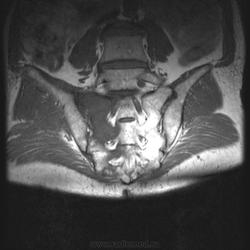

Мужчина, 60 лет. Направлен на МРТ пояснично-крестцового отдела позвоночника для исключения грыжеобразования. Жалуется на боли в правом тазобедренном суставе. Боли начались около месяца назад, сначала проявлялись в виде "неудобства", затем постепенно усиливались. В данный момент при объективном осмотре бережет ногу, хромает. Травмы, воспалительные заболевания отрицает.

При МРТ пояснично-крестцового отдела обратил на себя внимание крестец. Досмотрели крестец с контрастом. Хотелось бы услышать Ваше мнениие по поводу представленных снимков:

А по текущему случаю предложения будут? Не смущает ли кого-нибудь неровный косо-вертикальный гипоинтенсивный сигнал, в особенности заметный на постконтрастных корональных изображениях?

Я все-таки склоняюсь к стресс-перелому (что и указал на первом месте в заключении). Пытал товарища, он признался, что на даче поднимал какие-то тяжести. Онкологией не страдает, да и ничем в общем-то не болеет.

Согласен с Евгением, здесь похоже на патологическую перестройку по типу болезни Дойчлендера.